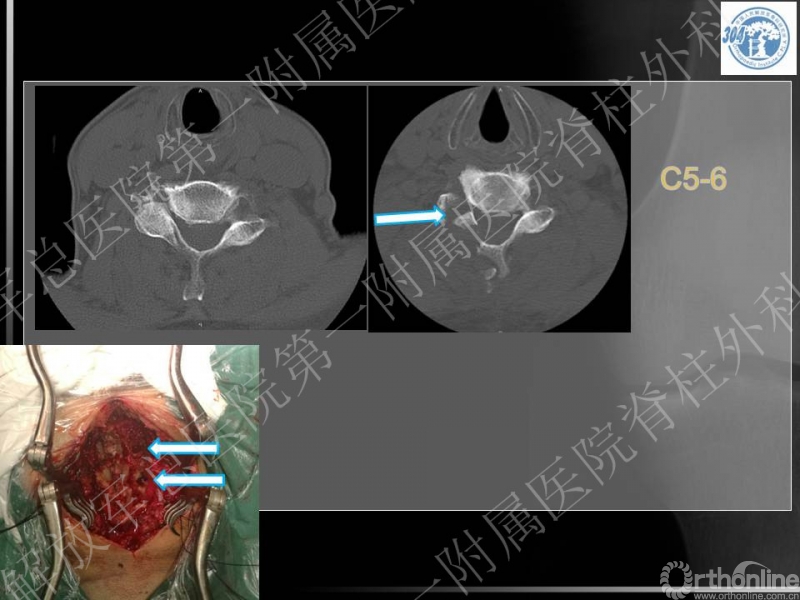

72岁 男性,既往体健,无严重基础疾病,6年前腰椎手术史

右侧前臂外侧及右拇指麻木疼痛,影响睡眠,超过3月不缓解,双手协调控制差

四肢关键肌肌力基本正常,肌张力增高,步态改变

腱反射亢进,双侧Hoffman征(+)

手术选择,前路,后路,前后联合?

手术节段和范围?

神经根出口狭窄是否需要处理?

术后资料:

本病例的特点为患者既往有颈椎病的基础,近期出现右上肢疼痛、麻木症状,老年,专家讨论要点主要集中在患者手术前后路选择,节段选择及手术时机等。

李放教授:

患者缺乏X光片颈椎管椎管比值的测量,但基本可见患者有明确的发育性颈椎管狭窄,又有颈椎退变增生的病理基础,核磁见多节段的颈脊髓压迫,近期出现右上肢疼痛麻木症状,体格检查脊髓和单一神经根损害表现,为混合型颈椎病(脊髓型/神经根型)。可考虑行颈椎管扩大成形术,包括单开门/双开门等方式,结合单一神经管切开减压,可达到全面的治疗效果。

蒋毅主任:

同意李放教授的观点,提出部分学者甚至认为单开门术中常规切开颈4-5神经根管,防止出现颈5神经根病。

党耕町教授:

同意以上观点,对郭继东副主任医师采取的短节段后路开门的治疗方案予以肯定。同时他提出根据老年患者对生活质量的需求,其可能仅想解除短期内的新发的上肢麻木症状,仅行责任节段的神经根管切开术。